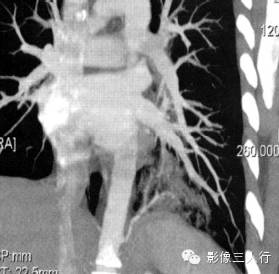

报告书写:扫描显示胸廓对称,左肺下叶脊柱旁见团块样病变,其内可见囊状空腔。双侧肺门不大,纵隔居中,其内未见肿大的淋巴结。心脏大小正常,胸壁软组织未见异常。增强及三维重建显示供应血管来自腹主动脉(图2)。

图2肺叶外型肺隔离症

(C)三维重建

①约2/3的病人隔离肺位于脊柱旁沟,多位于左下叶后段,少数为右下叶后段。上叶少见。增强扫描发现供血血管可确诊。